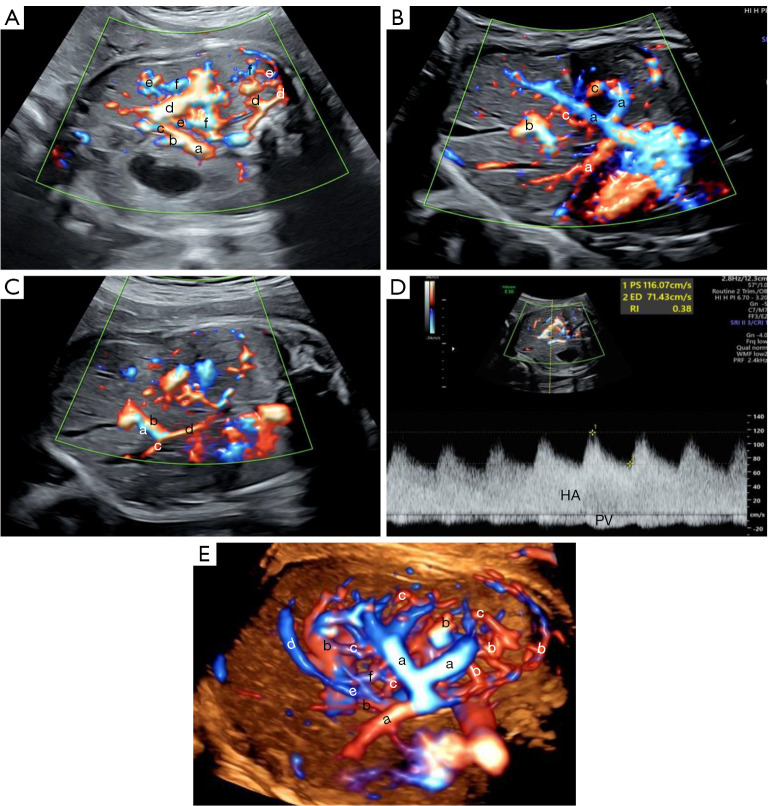

Prenatal discovery of hereditary hemorrhagic telangiectasia-associated hepatic arteriovenous malformations by multimodal ultrasound and whole-exome sequencing: a rare case description and literature analysis.